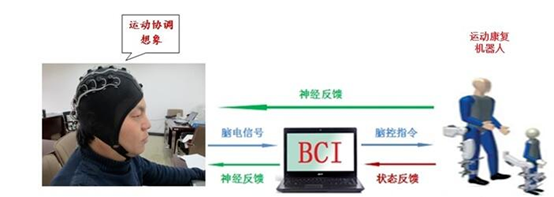

第二个因素是,在过去的50多年,从对动物和人类的研究中,人类对中枢神经系统(CNS)有了更多的理解,特别是关于大脑信号的本质与功能性相关的大量新信息,例如脑电活动和神经元动作电位。这些进步促进和稳步地指导更富有经验及富有成效的BCI研究。研究者理解了大脑具有非凡的适应能力,利用这种自适应能力,可能创建大脑与基于计算机的设备之间新颖的交互, 这种可能性令人十分兴奋,交互作用可以替代、恢复、增强、补充或改善大脑与它的内部和外部环境的自然交互。

第三个因素是, 对残障患者的需要和能力有了新的认识,他们因疾病而残疾, 如脑瘫、脊髓损伤、脑中风、肌萎缩性脊髓侧索硬化症(ALS)、多发性硬化症、肌肉营养不良症。BCI可望能够为有很少自主肌肉控制的人提供最基本的通信和控制方式,使得他们够享受令人愉快和富有成效的生活。